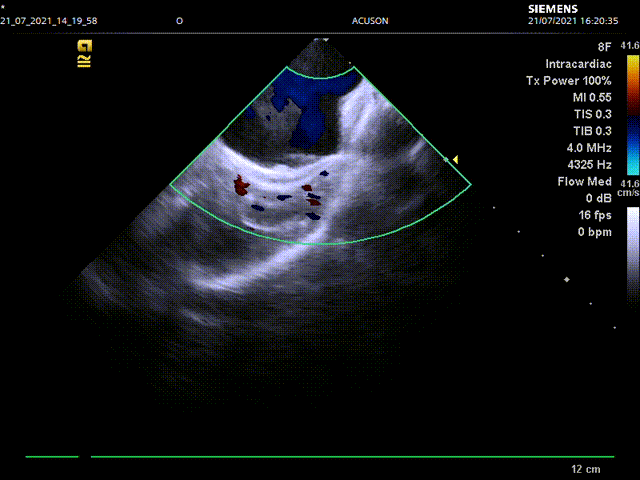

手术主要流程:经右股静脉入路,通过房间隔穿刺,将8F ICE导管送入左心房,在左心房通过三个不同的位置和角度测量左心耳锚定区大小和深度:左上肺静脉脊部角度、右肺静脉角度,二尖瓣环角度。而后进行左心耳造影,多种方式测量左心耳大小,选择合适病人情况的封堵器。放置左心耳封堵器后再用同样位置角度评估封堵情况。

心腔内超声左房内左上肺静脉嵴部测量左心耳开口锚定区和深度

心腔内超声左房内右肺静脉前测量左心耳开口锚定区和深度

心腔内超声左房内二尖瓣水平测量左心耳开口锚定区和深度

经测量,选用LAmbre 2638型号封堵器,在ICE指导下进行封堵,再进行左上肺静脉脊部、右肺静脉,二尖瓣环三个角度的封堵情况评估和牵拉测试,最终释放封堵器。

心腔内超声左房内左上肺静脉嵴部评估封堵情况

心腔内超声左房内右肺肺静脉前评估封堵情况

心腔内超声左房内二尖瓣水平评估封堵情况